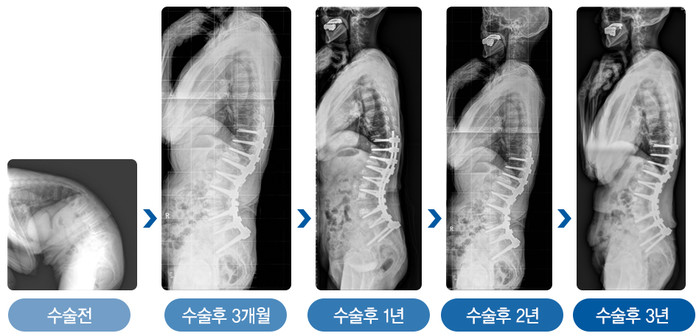

| ▲그림2. 심한 노인성 후만변형으로 수술을 받은 78세 환자 (여)는 수술 3년 후에도 허리곡선이 잘 유지되고 있다. |

김용찬 교수팀은 전방 추체 사이 유합술과 후방기기 고정술을 병합한 새로운 수술방법을 개발했다. 기존 수술 방법에서 추가적으로 추체 사이의 전방 종인대를 함께 부분 절제하는 수술법이다. 기존 추체절골술 후에 완벽한 구현되지 못했던 생리적 허리 곡선을 최대한 구현했으며, 빈번한 불유합으로 인한 재변형에 의한 재수술 발생을 획기적으로 감소시켰다. 또 수술 직후 얻었던 허리 곡선이 오랜 기간 동안 유지됨을 확인했다.

강동경희대학교병원 정형외과 김용찬 교수팀은 노인성 후만변형 환자(허리가 굽는 환자)의 합병증을 획기적으로 줄이는 새로운 수술적 기법을 개발해 그 시행결과를 발표했다. 김용찬 교수는 70세 이상 환자 38명을 대상으로 수술 시행 결과 기존 수술법에 비해, 1) 수술 직후 임상적‧방사선적 결과가 매우 우수한 것은 물론, 2) 수술 후 3년 이상의 기간 동안 허리가 다시 굽어지거나 뼈가 골절되는 부작용 및 합병증을 효과적으로 예방되었다고 밝혔다. 이는 2019년 대한척추외과학회 춘계학술대회 및 2019년 일본척추외과학회(Japanese Spine Society Research)에 발표했으며, 유럽 척추외과 학술지(European Spine Journal)에도 게재될 예정이다.